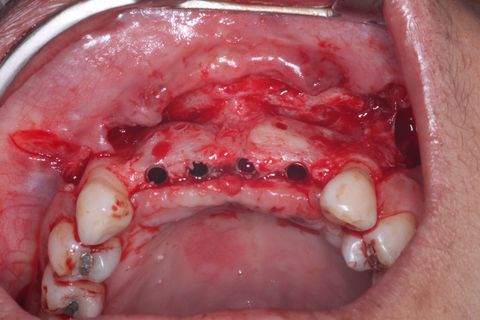

Novo procedimento cirúrgico após 6 mêses. Incisão

Descolamento Mucoperiosteal. Notar o ganho em expessura óssea.

Guia Cirúrgico e paralelizadores conferindo o ângulo de Fresagem/Inserção dos implantes